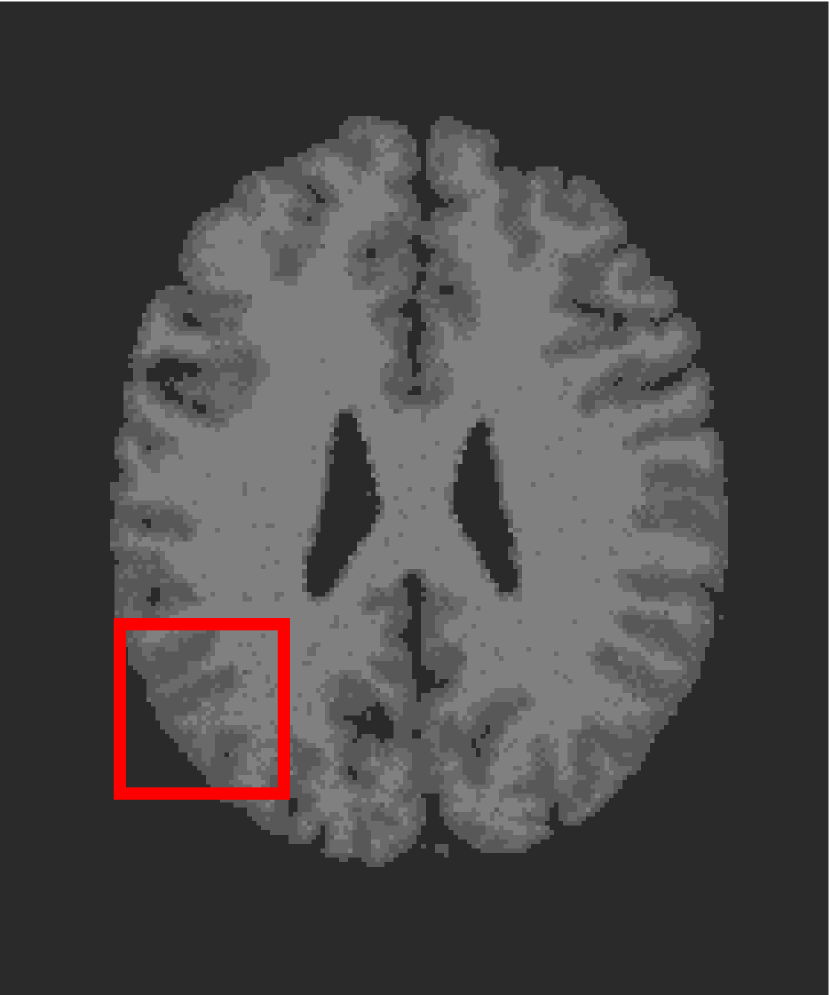

In the second experiments, we segment two medical images coming from a simulated brain database (BrianWeb): http://www.bic.mni.mcgill.ca/brainweb/. The two images are generated by T1 modality with slice thickness of 1mm resolution, 9% noise and 20% intensity non-uniformity. Here, the two images are represented two slices in the axial plane with the sequence of 100 and 110. Moreover, there are golden standard segmentations in the dataset. We set the numbers of clusters to 4. The visual comparisons are illustrated in Figs. 6 and 7.

Figure 7: Segmentation results for the second medical image. From (a) to (l): ground truth, noisy image and results of FCM_S1, FCM_S2, FGFCM, FLICM, KWFLICM, ARKFCM, FRFCM, WFCM, DSFCM_N, and LRFCM.

By focusing on the marked red square in Figs. 6 and 7, we easily find that FCM_S1, FCM_S2, FGFCM and ARKFCM are sensitive to noise. FLICM and KWFLICM are vulnerable to severe intensity inhomogeneity. FRFCM brings overly smooth results due to the use of gray level histograms. WFCM and DSFCM_N cause several contours to change. However, LRFCM acquires clear contours and suppresses noise adequately. Moreover, we find that the segmentation result of LRFCM is closer to ground truth.